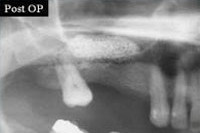

Knochenaufbau